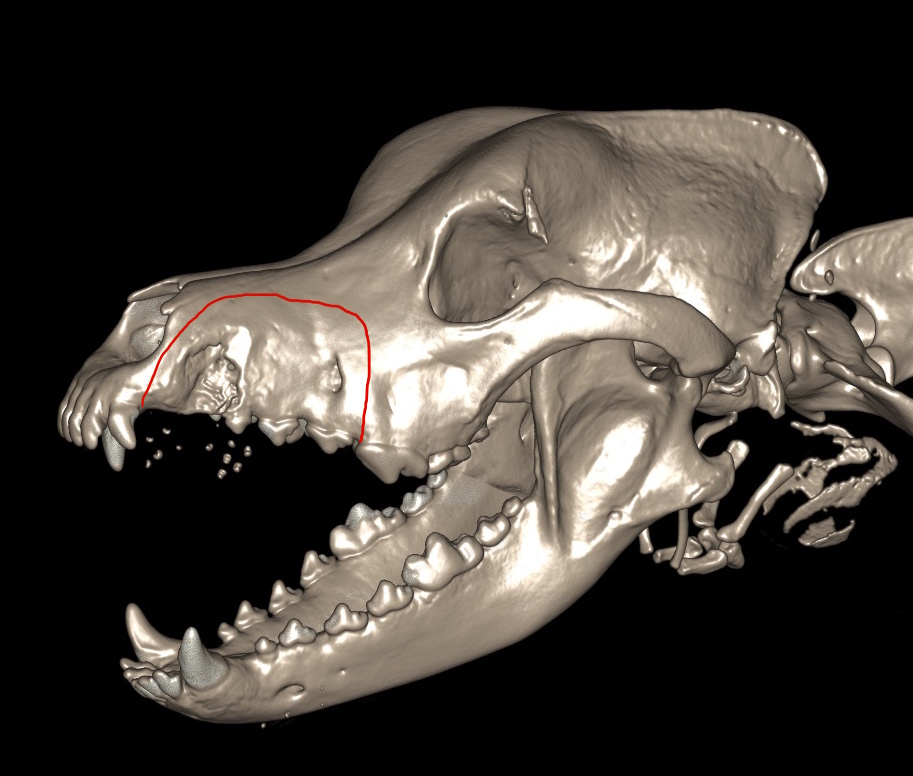

Um die Operation sinnvoll planen zu können war es wichtig zu wissen, wie der darunterliegende Knochen aussah - ob der Tumor bereits begonnen hatte, diesen zu zerstören und wie weit der Tumor sich auch im umliegenden Weichteilgewebe ausgebreitet hatte. Daher wurde bei Buma zunächst eine Computertomographie (CT) durchgeführt. Der CT-Befund zeigte eine Knochenbeteiligung im Bereich des zweiten Backenzahnes, jedoch weder einen Einbruch in die Nasenhöhle noch eine Veränderung der zuständigen Lymphknoten.

Anhand der 3D-Rekonstruktionen der Computertomographie wurde ein Operationsplan erstellt. Aufgrund der Tumorart war klar, dass es nicht ausreichen würde den Tumor nur oberflächlich bzw. mit geringem Abstand zu entfernen. Daher wurde die Entfernung des linken Oberkieferknochens inklusive der Zahnreihe beginnend vom dritten Schneidezahn bis zum großen Reisszahn (P4) geplant.